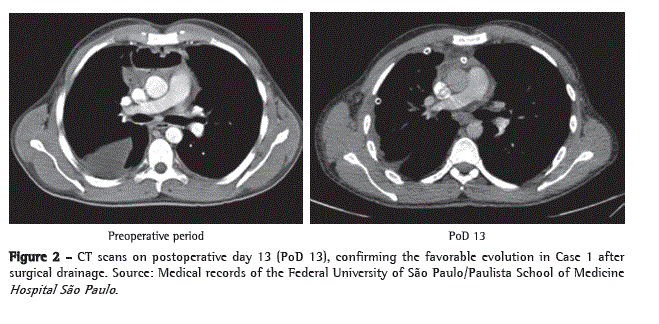

Physical examination on admission to the emergency room revealed pallor (2+/4+); tachypnea (22 breaths/min); normal blood pressure (110 × 60 mmHg); cervical edema and phlogosis; dullness to percussion over the base of the right hemithorax (RHT); absent breath sounds in the middle and lower third of the RHT; and tachycardia (124 bpm). However, cardiac auscultation revealed no abnormalities. General laboratory tests showed leukocytosis (16,900/µL), with 9% rods and 81% neutrophils, thrombocytosis (756,000/µL), increased levels of C-reactive protein (225.9 mg/L), and increased ESR (92 mm/h). A chest X-ray revealed upper mediastinal widening, opacification of the lower two thirds of the RHT, and enlarged cardiac silhouette. The patient subsequently underwent CT of the neck and chest, which revealed large gaseous collections, initiating at the cervical region and extending along the left carotid sheath, spreading into the anterior and middle mediastinum, the pericardium, and the right pleural cavity (Figure 1).

We opted for therapy with broad-spectrum antibiotics (imipenem, cilastatin, and vancomycin) and emergency surgical exploration. The patient was placed in a semi-seated position, with outstretched arms, and his RHT was elevated 30° with the use of cushions. We opted for simple orotracheal intubation. We began with collar cervicotomy at the level of the cricoid cartilage to explore cervical compartments and continued to explore up to the base of the mandible, from where the infectious focus originated. Subsequently, we performed a 1.5-cm thoracotomy incision in the seventh right intercostal space (RIS), introduced a 10-mm fiberoptic bronchoscope (30°), and performed a 6.0-cm accessory anterior minithoracotomy incision in the fourth RIS, through which the entire pleural cavity was cleaned, the mediastinal pleura was opened, and all purulent fluid was drained. We placed an 18 F tube (airtight seal) in the anterior mediastinum and two tubes (water seal) in the pleural cavity-a posterior 18 F tube and an anterolateral 28 F tube. In the cervical region, we placed a Penrose drain, creating communication between the surgical site and the anterosuperior mediastinum, as well between the surgical site and the right pleural cavity, through the pretracheal fascia. Subsequently, the patient was referred to the ICU, where he remained under mechanical ventilation and received low doses of vasoactive drugs. The evolution was favorable, mechanical ventilation and the use of vasoactive drugs were discontinued on postoperative day 2, and the patient was discharged from the ICU on postoperative day 3 (Figure 2). The patient was

discharged from the hospital in good general health on postadmission day 18, without the need for further surgical intervention (Figures 3a and 3b).